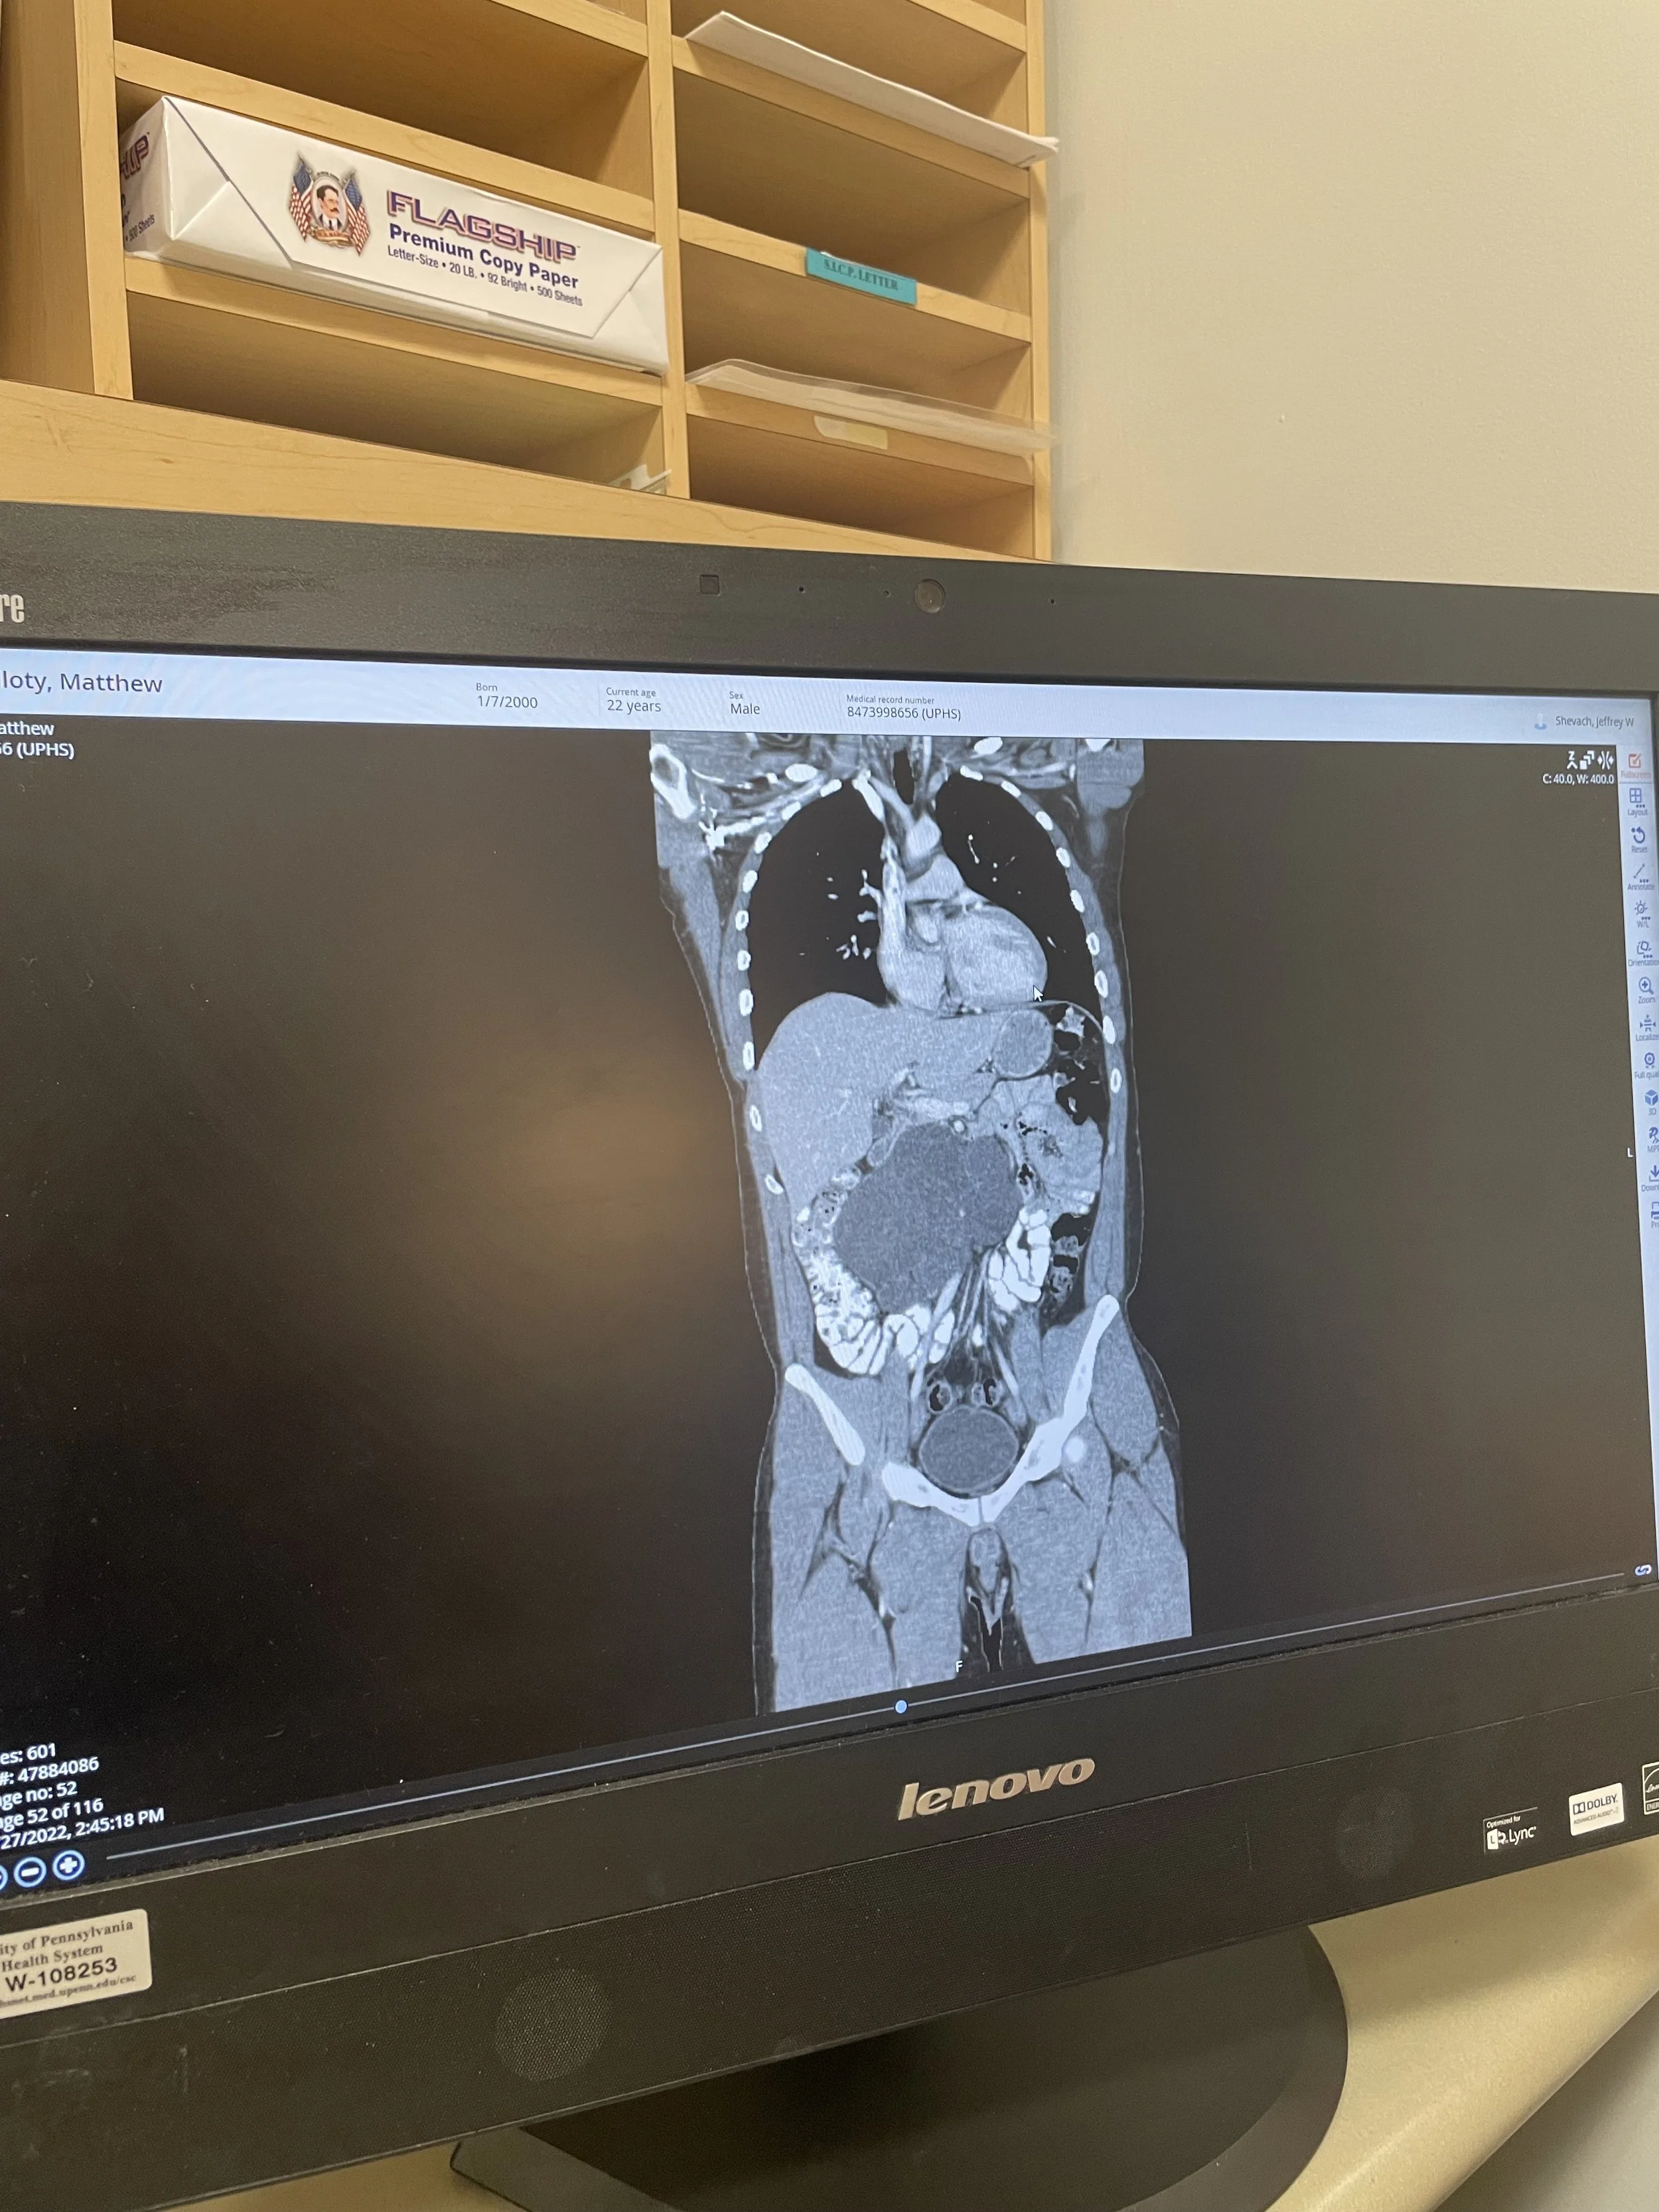

In this episode of It Takes Balls, Matt Guilloty shares his intense journey through stage IIIB non-seminomatous testicular cancer. What he believed was a hydrocele kept growing until his testicle reached “the size of an avocado,” eventually leading to a shocking diagnosis delivered while he was driving on the highway. Matt describes the moment he learned his AFP tumor markers were 3,389, his cancer had spread to lymph nodes and lungs, and he needed BEP chemotherapy.

Matt opens up about the physical and mental toll of four rounds of chemo - nausea, hiccups, fear before each cycle - and how he juggled treatment with grad school. He reflects on finding support through nurses, fellow survivors, and online communities, and how skateboarding helped him stay grounded. Matt also revisits his major post-chemo RPLND surgery and his long recovery back to mobility and strength.